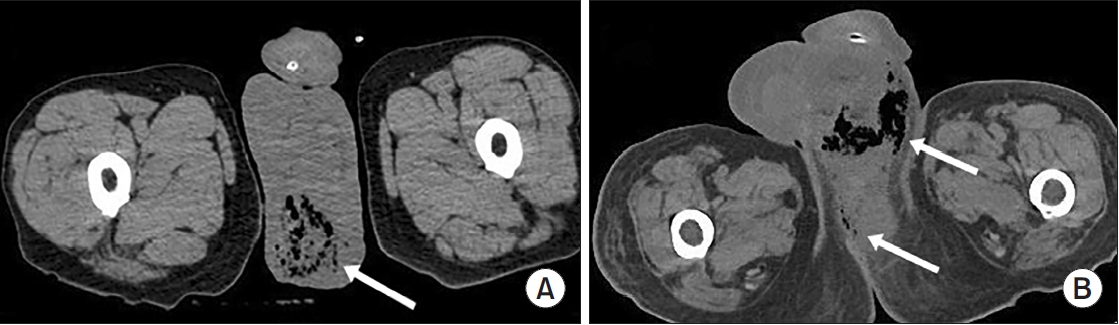

Cyclic Hematuria Misdiagnosed as Hemorrhagic Cystitis in a Rare Case of Vesicouterine Fistula Post-Cesarean Section: A Case Report of Youssef Syndrome

Vesicouterine fistulas are rare complications that may occur following cesarean sections and are frequently misdiagnosed due to their diverse clinical presentations. This report presents a case involving a small vesicouterine fistula initially managed conservatively, which later manifested as cyclic hematuria mimicking hemorrhagic cystitis, ultimately leading to a diagnosis of Youssef syndrome. A 45-year-old woman developed persistent vaginal urinary leakage 3 weeks after a cesarean section. Diagnostic evaluation confirmed a small (<1 cm) vesicouterine fistula. Conservative management with Foley catheterization resulted in spontaneous closure. Four months later, the patient experienced cyclic gross hematuria and dysuria without menstruation, and was subsequently diagnosed with Youssef syndrome. Hormonal therapy using continuous oral contraceptives successfully resolved the hematuria, providing a noninvasive therapeutic option. This case highlights the importance of considering Youssef syndrome in patients with cyclic hematuria after cesarean section, in order to distinguish it from hemorrhagic cystitis and ensure timely, appropriate management.